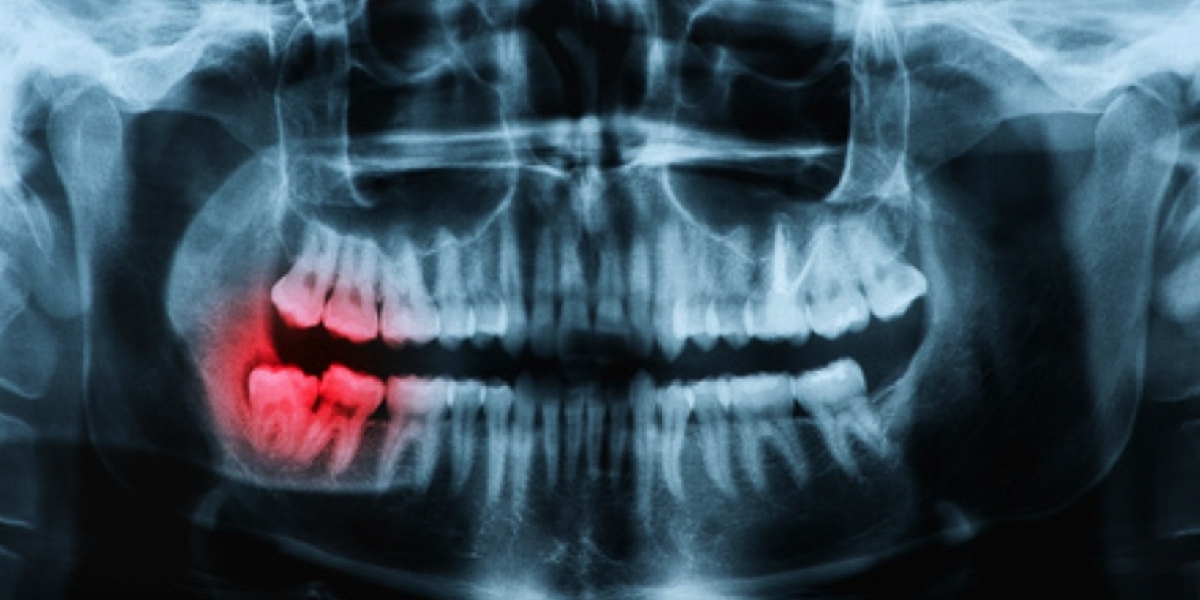

Teeth whitening is a non-invasive procedure designed to lighten the color of natural teeth. It works by breaking down stains and discoloration using safe bleaching agents. The process begins with a thorough panoramic dental examination duration in Dubai (مدة فحص البانورامية للأسنان في دبي), which allows dentists to evaluate the teeth and identify areas that require treatment. Unlike regular dental X-rays, Panoramic dental X-rays versus regular dental X-rays in Dubai (البانورامية للأسنان مقابل الأشعة العادية في دبي) provide a complete view of the jaw, teeth alignment, and bone structure, ensuring that whitening is suitable for the patient. This method prevents complications, such as uneven whitening or underlying dental issues going unnoticed.